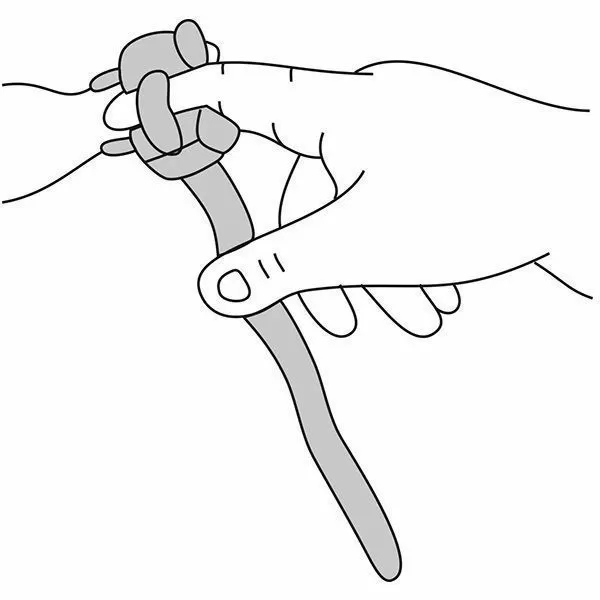

Почему может врать пульсоксиметр?

Причин, по которым пульсоксиметр может проводить измерения неверно, бывает несколько:

- у вас холодные руки. Согрейте их перед измерением;

- вы не до конца поместили палец внутрь прибора или измерению мешает длинный ноготь. Толстый слой гель-лака тоже может быть препятствием;

- вы долго находились в медицинской маске. Снимите ее, подышите глубоко и после этого делайте замер.